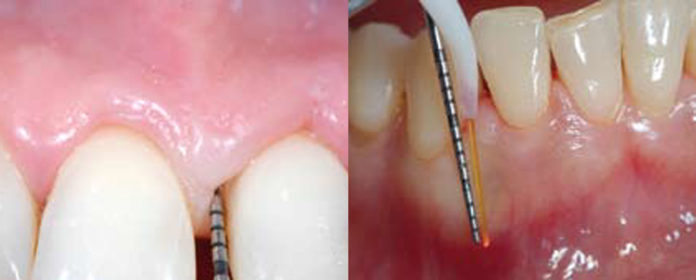

Nella fase strumentale è opportuno utilizzare tecniche e mezzi di ultima generazione, come per esempio il laser a lunghezza d’onda compresa tra 808 e 980 nanometri, nello spettro dell’infrarosso, con sorgente all’arsenuro di gallio, più comunemente chiamato diodo. Il laser a diodo dimostra buona affinità per i tessuti molli, può andare a diretto contatto con le superfici implantari e può essere utilizzato nel trattamento delle perimplantiti di natura batterica, di grado lieve o moderato.

- il Laser a Diodi come ausilio alla Strumentazione Parodontale Non Chirurgica: indicazioni, limiti e protocolli;

- tecnica operativa;

- il laser nel trattamento delle perimplantiti di natura batterica, di grado lieve o moderato;